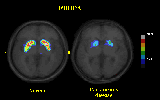

The mechanisms that couple neuronal activity to blood flow and oxidative metabolism are not yet known. An apparent uncoupling of blood flow from oxygen metabolism during brief phasic stimulation of somatosensory and visual cortex has been demonstrated by several workers. The prediction was that selective visual stimuli may elevate oxidative metabolism in regions of visual cortex with a high content of cytochrome oxidase. To test this prediction, oxygen metabolism and blood flow were measured in normal volunteers after different durations of tonic stimulation. The stimulus was a semi annular reversing contrast checkerboard pattern visible only to the left visual field of the left eye between 5 and 20 degrees of visual angle and at a retinal eccentricity of about 15 degrees (See Figure 7). Oxygen consumption increased significantly in the primary visual cortex after 3-5 minutes and after 8-10 minutes of stimulation (See Figure 8). The result is consistent with a stimulus specific modulation of oxidative metabolism in neurons with a higher than average content of cytochrome oxidase. CBF = cerebral blood flow. CMR = cerebral metabolic rate.

Figure 7: The semiannular checkerboard stimulus presented to the subjects.

Figure 8: An example of the PET results showing increased oxygen consumption.